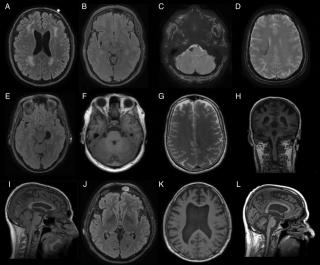

Диагноз спонтанной спинальной эпидуральной гематомы обычно верифицируется с помощью МРТ или компьютерной томографии в сочетании с миелографией. Спинальная ангиография в настоящее время редко используется для таких ургентных случаев, как острая спинальная эпидуральная гематома. Магнитно-резонансная томография (МРТ) является основным методом в диагностике СЭГ. Типичная МР-картина СЭГ заключается в визуализации экстрадурального объемного образования двояковыпуклой формы с четко определенными границами, сужающихся кверху и книзу. В первые 24 часа СЭГ равномерно изоинтенсивна на Т1 взвешенных изображениях, а на Т2 ВИ как правило гиперинтенсивна, но в некоторых случаях может иметь неоднородный сигнал. По истечению 48 часов, в подострой стадии, гематома, как правило, дает гетерогенный гиперинтенсивный сигнал как на Т1 ВИ, так и на Т2 ВИ. Усиление неоднородности сигнала происходит в результате образования дезокси-гемоглобина.

МРТ головного мозга. Т1-взвешенная аксиальная МРТ. Субдуральная гематома. Цветовая обработка изображения.

Диагностика состоит в выполнении КТ и МРТ головного мозга. Отображение крови на МРТ зависит от сроков.

МРТ головного мозга. Аксиальная Т2-взвешенная МРТ. Кровоизлияние в мозжечок.

МРТ головного мозга. Т1-взвешенная корональная МРТ. Смешанный ишемический инсульт. Ранняя подострая стадия.

МРТ головного мозга. Аксиальная МРТ типа FLAIR. Аневризма и САК, внутрижелудочковое кровоизлияние.

МРТ головного мозга. Диффузионно-взвешенная МРТ последовательность. ОНМК в острой стадии вследствие вазоспазма.

МРТ головного мозга. Аксиальная Т2-взвешенная МРТ. Подострая субдуральная гематома.

КТ. Эпидуральная гематома.

МРТ головного мозга. Аксиальная Т2-взвешенная МРТ типа FLAIR. Внутрижелудочковое кровоизлияние.

МРТ головного мозга. Корональная Т1-взвешенная МРТ. Апоплексия макроаденомы гипофиза с кровоизлиянием.